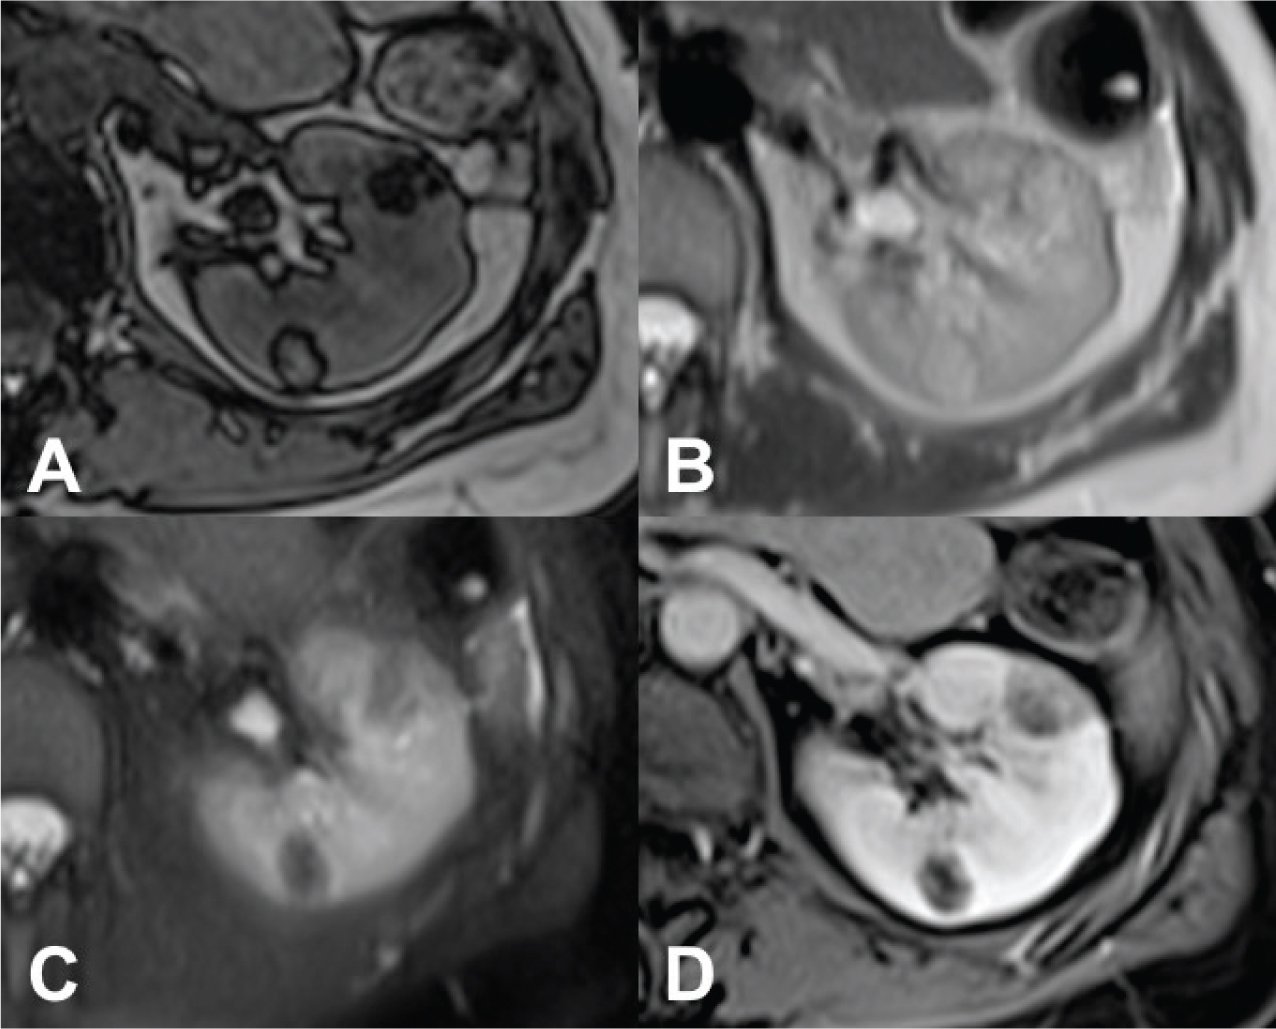

On magnetic resonance imaging (MRI), it appears isointense compared with fat on T1-weighted images; moreover, with the use of in-phase and opposed-phase imaging, AMLs with predominant adipose component show the characteristic India ink artifact that appears at the interface between the lesion and the normal renal parenchyma on opposed-phase T1-weighted images. In T2-weighted images, however, the intensity can be variable, depending on the amount of adipose tissue present in the lesion, resulting homogeneously high in AMLs with a higher adipose component (Figure 2) (5154).

Fig 2

Figure 2. MRI axial scan of the abdomen shows two AMLs of the left kidney. (A) Opposed-phase shows the characteristic India ink artifact of the AMLs. (B) AMLs appear hyperintense on T2-weighted images and (C) hypointense on T2-weighted images with fat suppression. (D) T1-weighted image with fat suppression shows contrast enhancement of the AMLs.